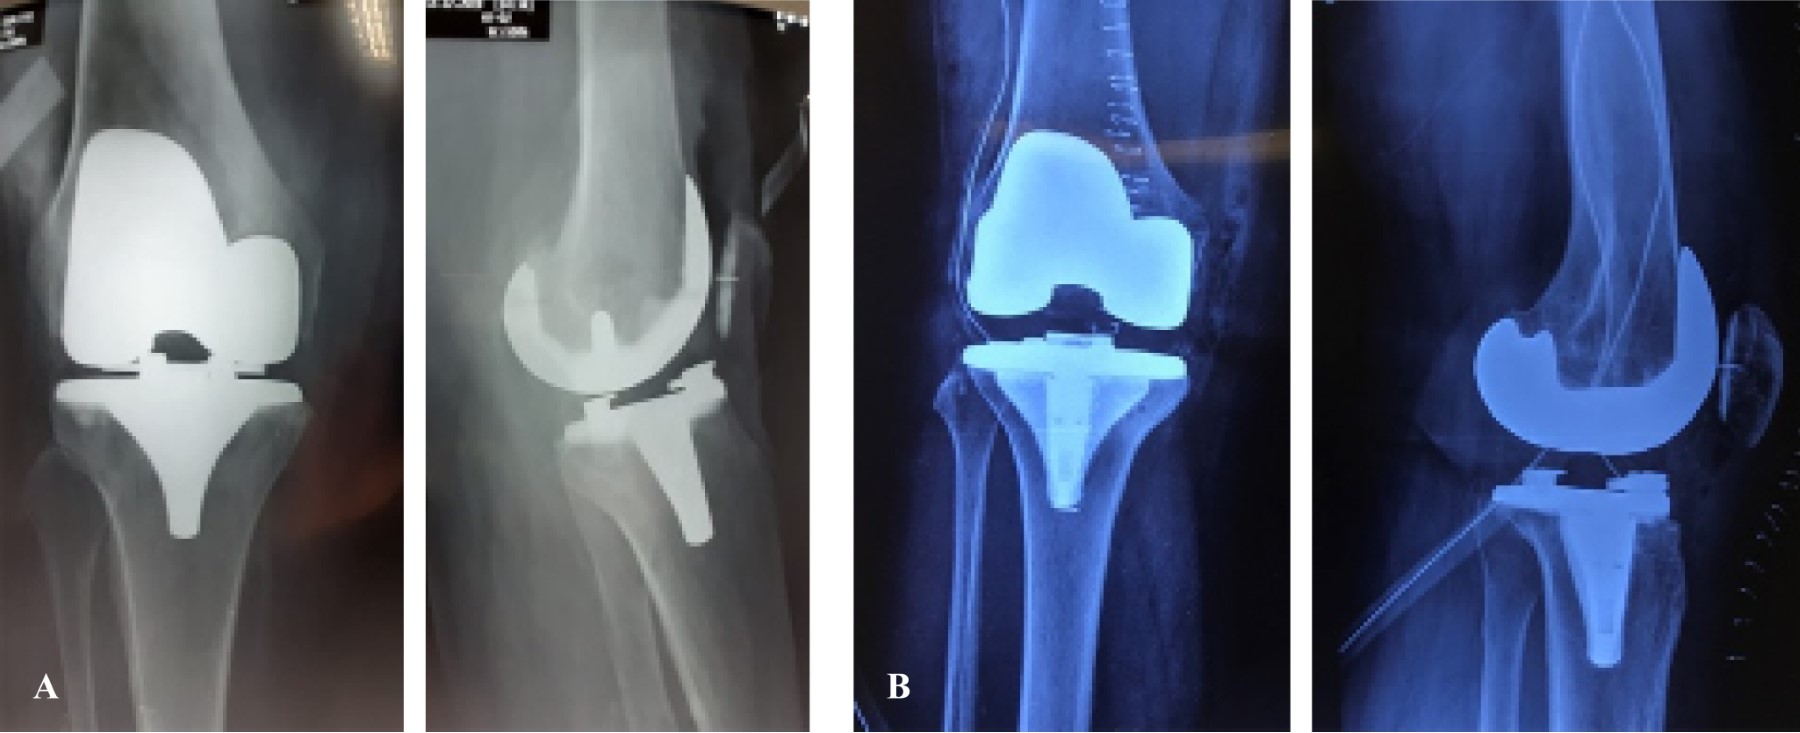

Figure 1

Figure 2

Figure 3